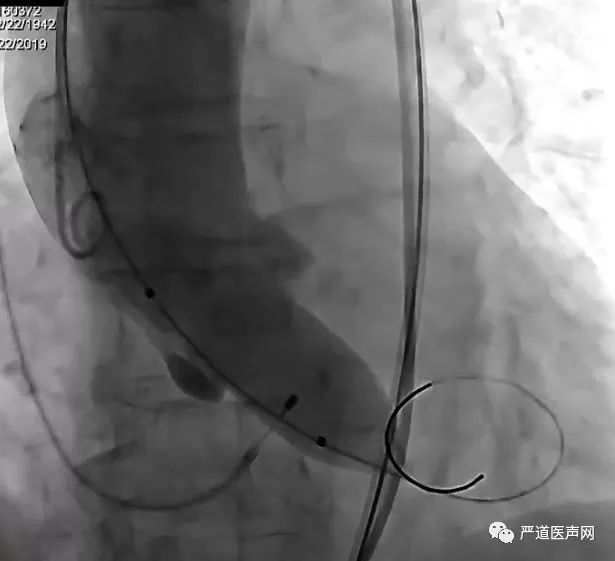

全麻气管插管,通过右颈内静脉留置临时起搏器于右室,以右侧股动脉作为主入路,经皮穿刺,预置2把Proglide缝合器。主动脉根部造影可见主动脉瓣钙化影,主动脉瓣中-重度返流。

TAVR术前主动脉根部造影

送入猪尾导管至左心室,测量左室压力150/12mmHg,升主动脉压力110/35mmHg,跨瓣压差40mmHg。交换头端预塑形Cook Lunderquist超硬导丝至左心室,撤出猪尾导管。(如下图)

心脏临时起搏器快心室率起搏下启用23mmCRISTAL球囊行主动脉瓣球囊预扩张,再次行主动脉根部造影,提示球囊无腰征,并有部分造影剂渗漏。(如下图)